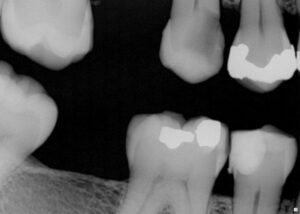

Extreme DME case using the Rhondium DME wedge in sequence with the Garrison Compositight system with a supercomposite placed incrementally to support what little is left of this extremely-compromised second bicuspid.

#VocoGrandioSO #RhondiumDME #GarrisonCompositight